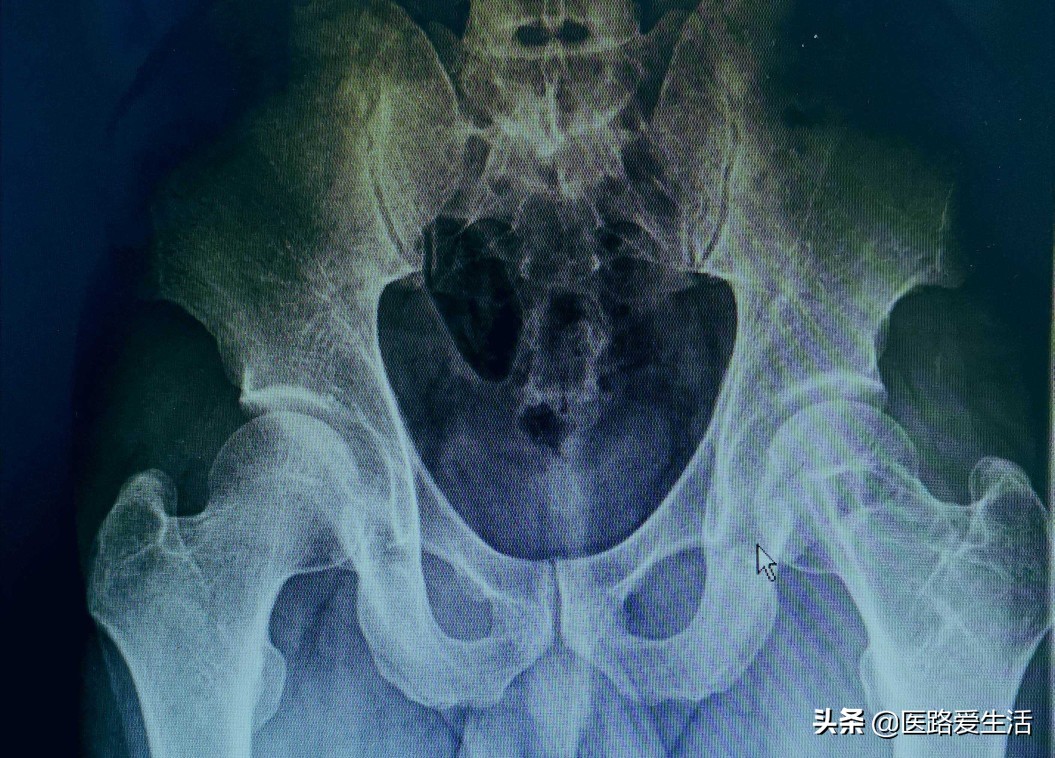

检查:1.最基本的X线检查可反应骨与软组织基本问题。

2.还有CT可提示病变的横断面影像。